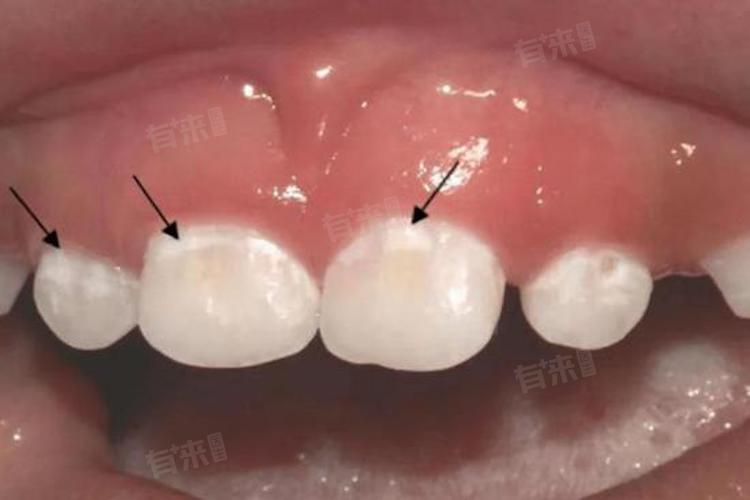

牙齿脱矿的补救方法包括再矿化治疗、树脂修复与全冠修复等。轻微脱矿可通过再矿化治疗改善,严重脱矿则需全冠修复,选择合适补救方法,可有效恢复牙齿健康。

1、再矿化治疗:再矿化治疗是牙齿脱矿的初步补救方法,适用于脱矿程度较轻、牙齿表面无明显缺损的情况。通过在专业医生的指导下局部使用含氟物质,进行局部涂氟,促进牙齿表面的矿物质重新沉积,从而恢复牙齿的硬度和光泽。